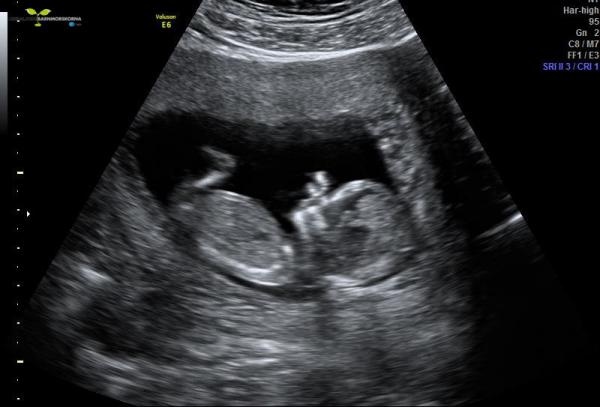

En liten sprattlande bebis där inne :D blev flyttad bak 3 dagar nu :P svårt att bestämma sig, men nu är jag beräknad till 10/12 och är i vecka 13, 12+3. Risken var enligt barnmorskan låg, 1:5164.